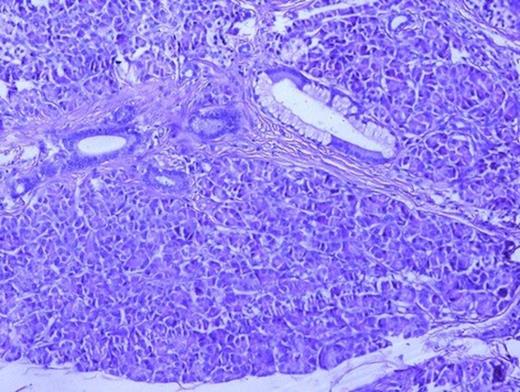

Surgical specimen of resected ileal polyp with adjacent bowel loop (1a) cut surface of which was pale yellow (1b). Histological examination revealed presence of pancreatic tissue in muscularis propria of ileum (1c) (H&E, x40) with overlying mucosa showing congestion and metaplasia (1d) (H&E, x40)

On gross examination, the polyp was brown, oval sessile mass with a broad base measuring 6×3.5×2 cm (Fig. 1a). On dissection cut surface was pale yellow (Fig. 1b). The histological examination revealed the presence of pancreatic tissue in the muscularis propria of ileum (Fig. 1c) made up of pancreatic acini and dialated ducts interspersed by smooth muscle bundles (Fig. 2). The overlying mucosa showed congestion and metaplasia (Figure 1d). Islets of Langerhans were not demonstrated.